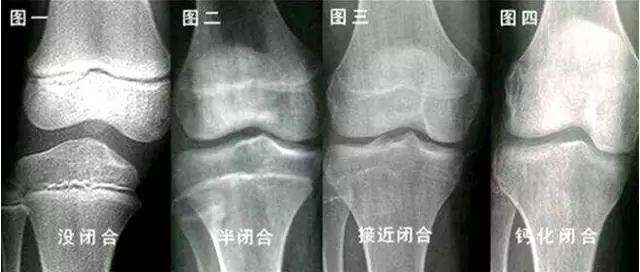

1、骨骺線閉合定義:骨骺線是指兒童在生長發(fā)育過程中,骨骼生長板處的特殊結(jié)構(gòu),隨著生長發(fā)育的進(jìn)行,骨骺線逐漸閉合,標(biāo)志著骨骼生長的停止。